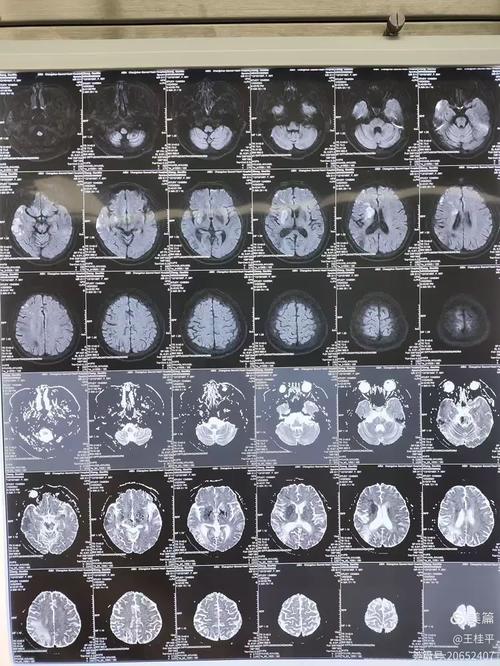

| 脑MRI (磁共振) | 对早期脑梗极其敏感,发病后1-2小时即可发现异常。 无辐射。 对小脑、脑干等部位的病灶显示清晰。 能区分新旧病灶。 |

对早期脑梗:发病后数小时内 |